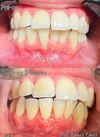

نزيف اللثة

أمراض الأسنان واللثة

التهاب ما حول الزرعة السنية (Periimplantitis)

التهاب مخاطية ما حول الزرعة السنية (Peri-İmplant Mukozitis)